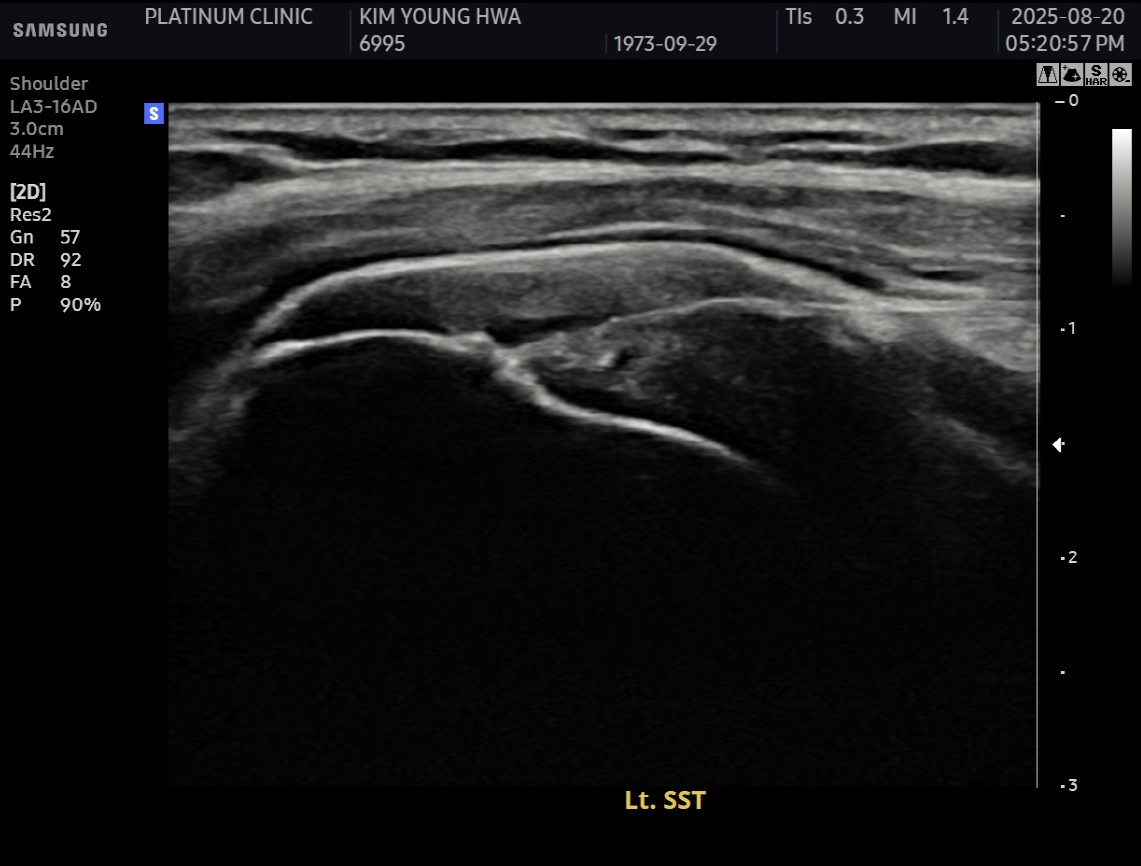

X-ray와 MRI, 초음파 검사를 시행했습니다.

진단 결과:

- ✓석회성건염: 극상건에 약 1.4cm 석회 (휴지기)

- ✓회전근개 관절면측 부분파열: 약 40%

두 가지 문제가 동시에 있었습니다.

10주 후 초음파:

봉합 부위가 정상 인대처럼 하얗게 재생되어 있었습니다. 골수자극의 효과로 예상보다 빠른 재생이 확인되었습니다.